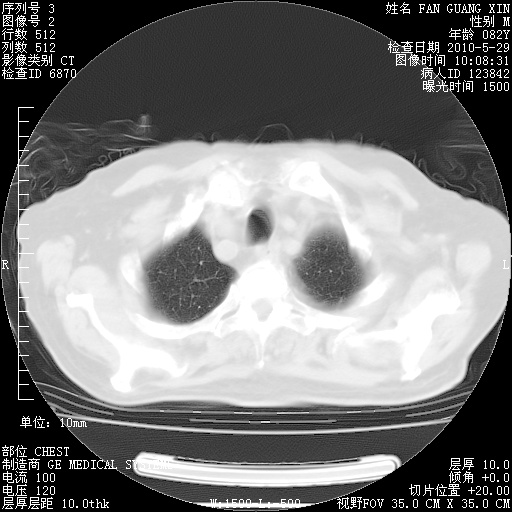

再治疗10天后的肺部CT

再治疗10天后的肺部CT 纵膈窗

阅读此次胸部CT,肺间质渗出性改变较入院时有吸收。目前从体温、白细胞、中性分叶明显增高,肯定存在细菌感染(发生医院感染哦,若无消化道及泌尿系统等感染的依据,肺部感染可能大)。若你院头孢哌酮舒巴坦钠耐药率较高,同意你的方案,若48小时体温仍高,可考虑使用碳青霉稀类抗菌药物,同时可予超声雾化、注意滴数时加大液体量。白蛋白33.30g/L较低哦,需加强营养等支持治疗。